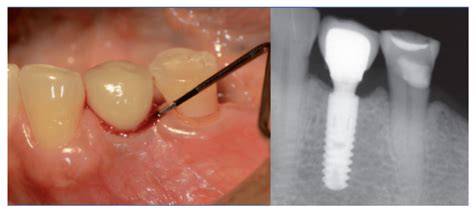

Para tratar las infecciones en los implantes dentales es necesario determinar, en primer lugar, su causa y gravedad. Este es el principal tratamiento contra la mucositis periimplantaria, es decir, las infecciones más leves que afectan únicamente al tejido blando (encías), y también para el tratamiento de desinfección inicial en la periimplantitis. En estos casos, se lleva a cabo una desinfección subgingival, que consiste en realizar una limpieza profunda debajo de la línea de las encías, lo que se hace mediante instrumental manual y mecánico.

Para ello, se separa el tejido blando que se encuentra alrededor del implante, se limpia la superficie del implante y se retiran las bacterias. Por lo general, resulta necesario acompañar el tratamiento quirúrgico con medicación antibiótica, que ayuda a controlar la infección provocada por la periimplantitis.

Tratamiento de la periimplantitis.